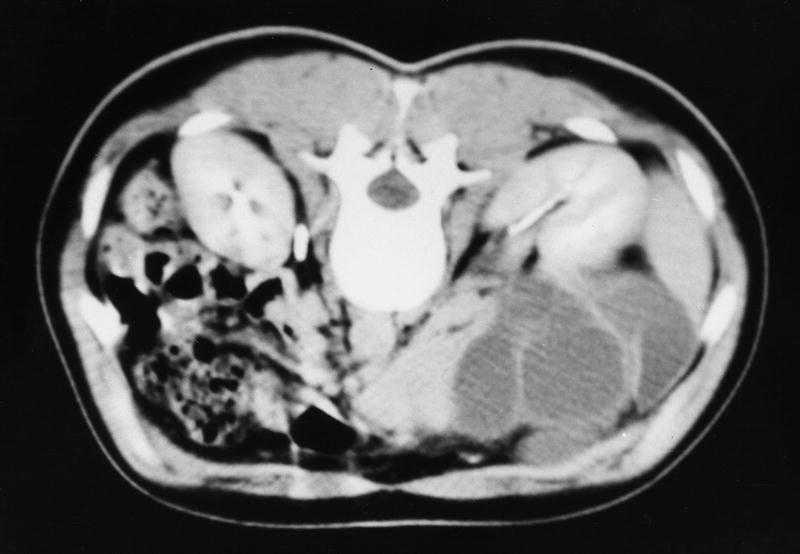

TAC abdominal. Imagen hipodensa tabicada que ocupa el hilio y el lóbulo hepático izquierdo, que comprime vesícula biliar y que estaba en contacto extenso con la vena cava inferior (fig. 2).

Fig. 2.